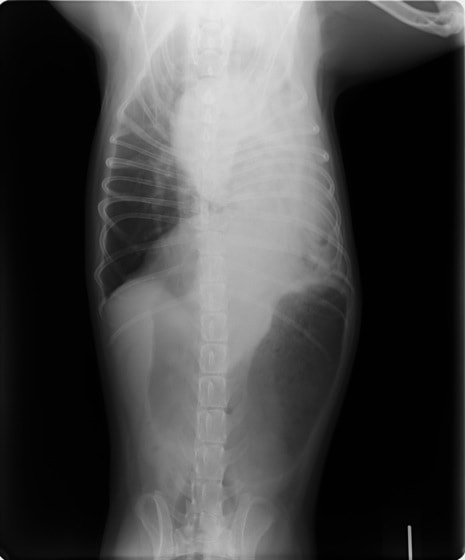

腹部と胸部を隔てている横隔膜が何らかの原因で裂け、腹部臓器(肝臓、小腸、胃など)が胸腔内に脱出してしまう病気です。脱出した臓器による肺・心臓の圧迫や、臓器の機能障害により、様々な呼吸器症状や消化器症状を示します。原因には外傷性と先天性の2つがあり、犬・猫で最も多いのは交通事故による外傷性横隔膜ヘルニアです。犬・猫の室内飼育が一般的になったことで交通事故が減り、それに伴い本疾患に遭遇することも減りましたが、屋外を自由に出入りしている猫では注意が必要です。屋外から帰った猫がお腹で呼吸をしている、苦しそうにしているなど、少しでも症状がある場合には早めに動物病院を受診し、レントゲン検査を受けられることをお勧めいたします。以下に交通事故が原因 と考えられる外傷性横隔膜ヘルニアの猫の症例をご紹介致します。

術前レントゲン

腹部臓器が胸腔内に脱出し、腹部と胸部の境界および心臓や肺の陰影が不明瞭になっています。また、胸腔内に消化管のガス陰影が認められます。

術後レントゲン

腹部臓器が腹腔内に戻り、腹部と胸部の境界および心臓や肺の陰影が明瞭に見えるようになりました。